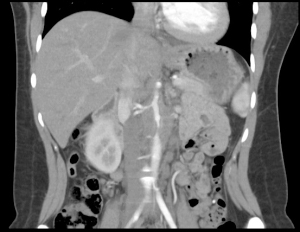

Patient underwent CT angiogram of her chest and abdomen emergently and the findings were suspicious for “periaortitis in association with midaortic syndrome with severe stenosis/near occlusion of the infrarenal aorta, bilateral renal arteries, celiac trunk, and SMA.” Findings that could represent a vasculitis versus neoplastic process.

Aorta computed tomography

Occluded aorta